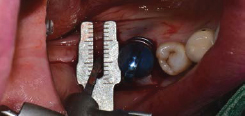

Point Drill 후 생성된 구멍에 Ø7.5 Volume Up Parallel Pin을 끼움

-

제조사의 식립 순서에 맞춰 Drilling 후 Fixture 식립

Fixture에 Volume Up Healing Abutment 체결